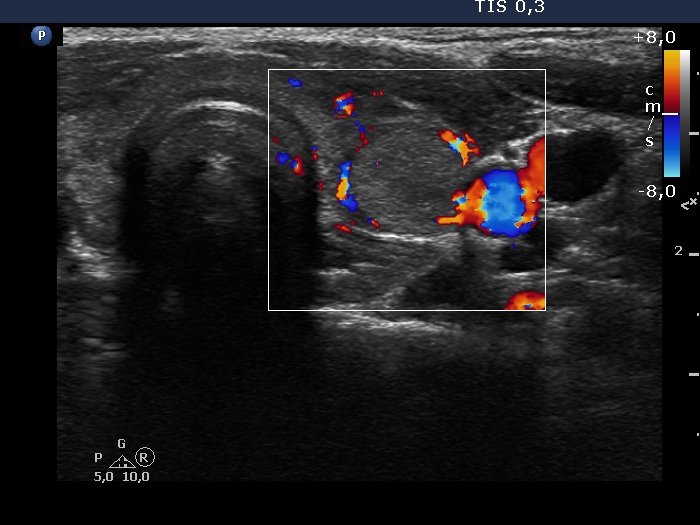

Left lobe, transverse view, color Doppler mode. The lesion presents perinodular blood flow.